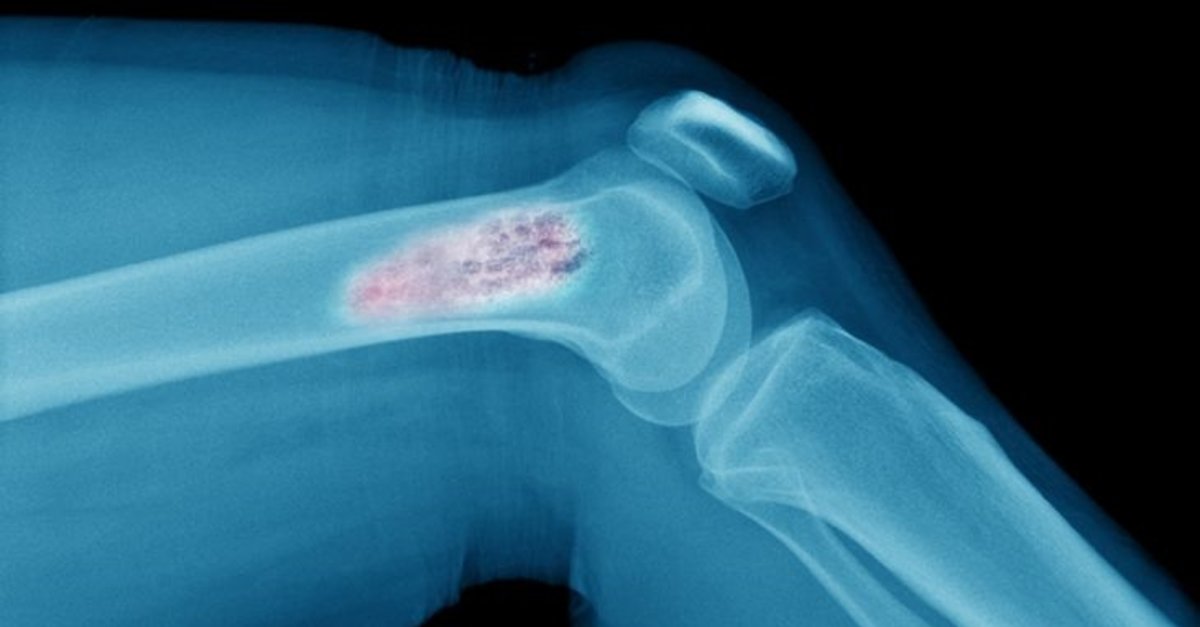

Nadir bir kanser türü olan kemik sarkomu olarak da bilinir ve vücuttaki herhangi bir kemikte büyümeye başlasa da çoğunlukla kol ve bacaklardaki uzun kemiklerde etki görülür. Bir kemik tümörü iyi huylu veya kanserli olabilir. Kanserli bir tümör büyüyecek ve agresif bir şekilde vücudun diğer bölgelerine yayılacaktır. Bununla birlikte, iyi huylu bir tümör büyür ancak vücudun diğer bölgelerine yayılmaz.

Kemik kanserleri ayrıca meydana geldikleri yere ve hücre tipine göre, bazıları diğerlerinden daha nadir olmak üzere birkaç türe ayrılabilir:

- Osteojenik sarkom; kollar, bacaklar veya pelvis kemik hücrelerinde başlama eğilimindedir ve tipik olarak 10-30 yaş arasındaki insanları etkiler.